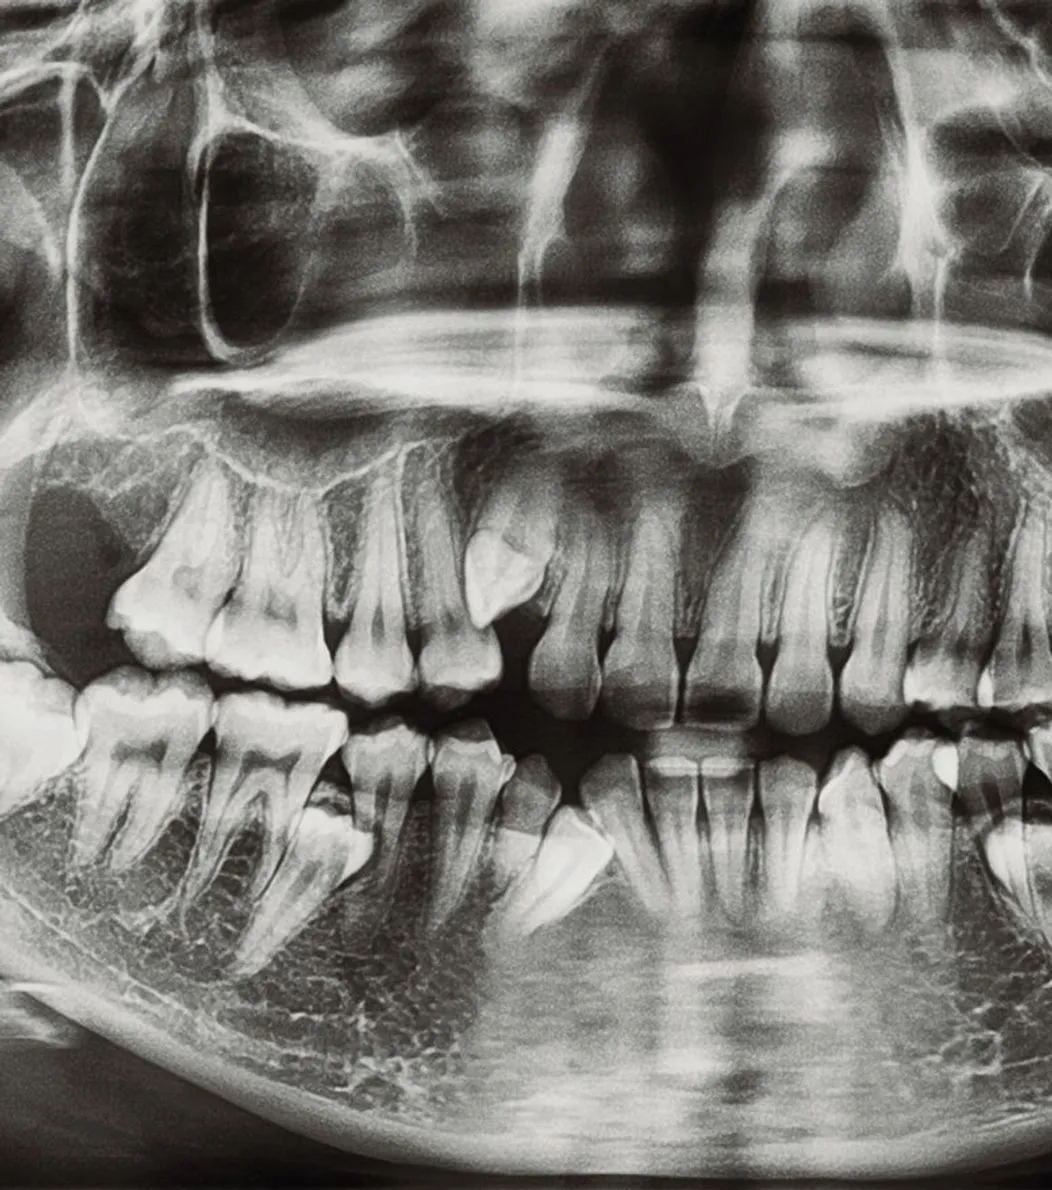

Dental implants provide a permanent, natural-looking solution for missing teeth. The implant is surgically placed in the jawbone, where it fuses with the bone for a secure and long-lasting fit. Implants help maintain bone density, restore function, and enhance aesthetics. With proper care, they can last a lifetime.